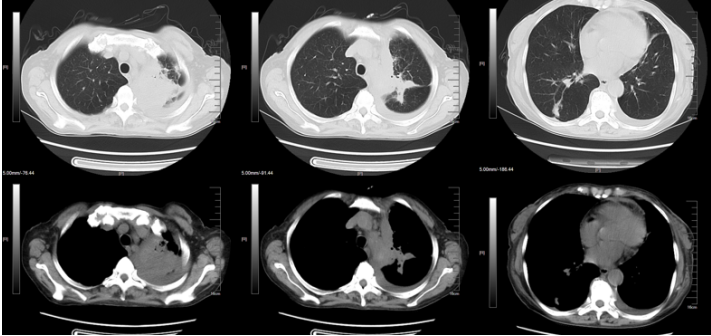

现病史:患者2024年1月7日左右无明显诱因下出现鼻塞等,外院胸部CT示:两肺炎症,肝内多发低密度灶。1月18日胸部CT:两肺散在渗出、斑点及空洞(图11)。当地医院予哌拉西林他唑巴坦抗感染,1月20日住院期间发热,热峰37.6℃,1月23日发热,热峰39℃,更换抗生素为头孢哌酮舒巴坦+左氧氟沙星,患者仍反复发热,1月25日达热峰38.4℃。

图11  患者胸部CT(2024-01-18)

1月31日复查胸部CT提示病灶进展,出现团块及空洞样改变(图12)

图12  患者复查胸部CT(2024-01-31)

2月9日再次复查胸部CT可见肺部弥漫及多发病灶较前吸收(图13)。患者症状改善,体温恢复正常,遂予出院,序贯艾沙康唑胶囊200 mg qd。

图13  患者复查胸部CT(2024-02-09)

3月16日门诊随访胸部CT: 双肺实变基本吸收, 右上肺仅余空洞、纤维条索样病灶(图14)

图14  门诊随访胸部CT(2024-03-16)